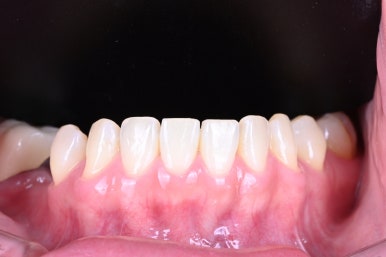

왼쪽이 위 앞니, 오른쪽이 아래 앞니 사진입니다.

분명히!! 가지런한 치아는 맞습니다.

앞니가 약간 짧은 느낌이 있습니다.

짧은 앞니는 어른보다는 아이같은 느낌을 주기 쉽죠.

그리고 전체적으로 약~간 네모난 느낌을 가지고 있는 것 같습니다.

하지만 또 엣지있을 정도의 네모난 치아 모양은 아니었어요.